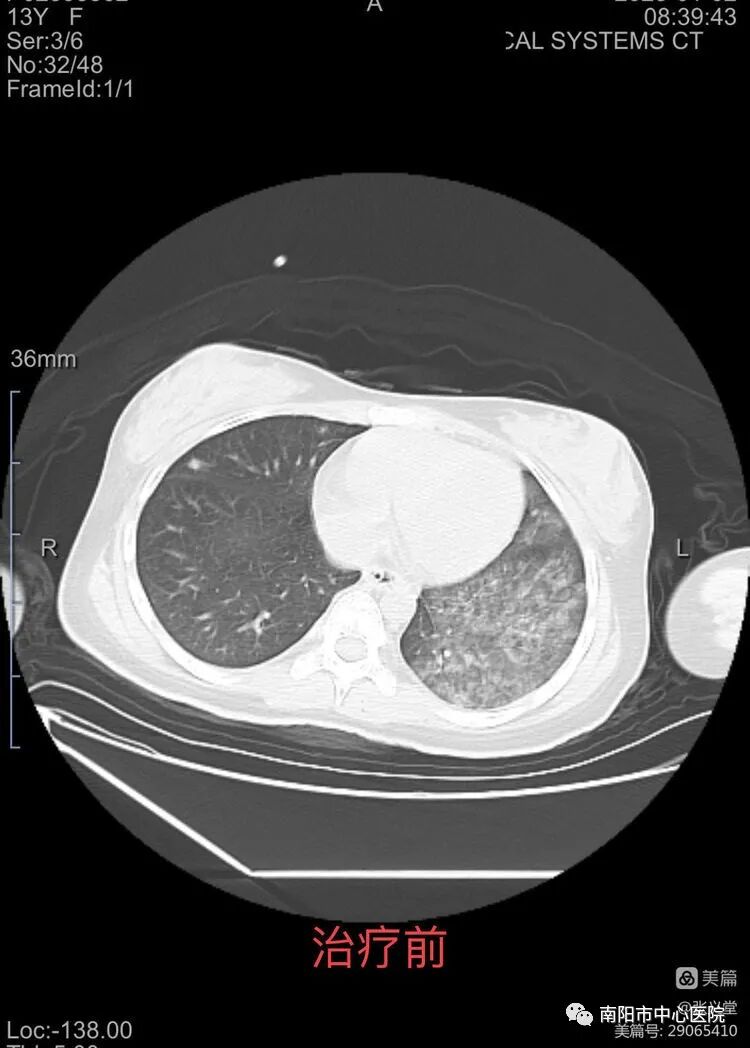

當(dāng)天11:30分,危重患兒送入了兒童重癥監(jiān)護(hù)病房,入院時患兒脫水貌,昏迷狀,呼吸困難,深大呼吸,心率快,四肢末梢涼。值班醫(yī)師仔細(xì)詢問病史,患兒最近發(fā)熱、咳嗽、精神差伴有氣喘、多飲多尿,前一天到外院住院,輸液治療后逐漸出現(xiàn)昏迷抽搐,當(dāng)即考慮患兒糖尿病合并酮癥酸中毒的可能性大,立即采末梢血糖32mmol/L,床旁血氣分析示PH 6.7,嚴(yán)重酸中毒??剖裔t(yī)護(hù)人員立即給予留置中心靜脈置管,建立靜脈輸液通道擴(kuò)容、監(jiān)測中心靜脈壓,補(bǔ)液糾正脫水、糾正酸中毒、胰島素持續(xù)泵注降糖。

經(jīng)過全體醫(yī)護(hù)人員的精心治療,日夜的守護(hù),患兒酸中毒糾正,肺部感染控制,患兒意識轉(zhuǎn)清楚,5天后順利撤除呼吸機(jī),12天患兒尿量逐漸增多,腎功能逐步恢復(fù),精神好轉(zhuǎn),已經(jīng)能自主進(jìn)食,各項生命體征穩(wěn)定,已轉(zhuǎn)入兒童內(nèi)分泌??普{(diào)理控制血糖。 在搶救過程中,科室及時向家屬反饋患兒病情,取得了家屬的積極配合。患兒母親更是淚流滿面、激動地說:“多虧來到南陽市中心醫(yī)院兒童重癥醫(yī)學(xué)科,感謝你們及時診斷,準(zhǔn)確救治,救了我孩子一命!” 近年來兒童糖尿病發(fā)病有增多的趨勢,兒童糖尿病大多數(shù)為Ⅰ型糖尿病,大多數(shù)兒童因為昏迷酮癥酸中毒就診,酮癥酸中毒是兒童糖尿病臨床常見的危急并發(fā)癥及其最常見死亡原因。年齡越小,臨床癥狀越不典型,病情越重,臨床表現(xiàn)復(fù)雜多變,極易漏診或誤診,早期診斷,正確治療對救治至關(guān)重要。南陽市中心醫(yī)院兒童重癥醫(yī)學(xué)科開科以來成功救治過多例糖尿病酮癥酸中毒的患兒,具有較高的技術(shù)和豐富的臨床經(jīng)驗。此次患兒的成功救治,再次彰顯了兒童重癥醫(yī)學(xué)科在救治急危重癥病例的能力和技術(shù)水平。